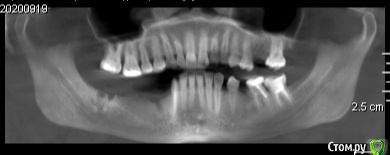

Екатерина Ч. Опубликовано 10 октября, 2020 Поделиться Опубликовано 10 октября, 2020 Здравствуйте. У меня при широком открытии рта в хрустит в челюсти. Что это может быть? Планирую делать имплантацию зубов на нижней челюсти не будет ли из-за этого проблем. У ортодонта не была. А имплантолог ничего не сказал. Ссылка на комментарий